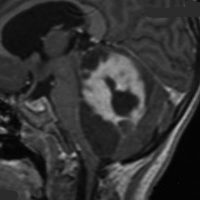

4歳発症の大きなもの

これも小脳中部上端から発生したもので,中脳水道が開いています。OTAで摘出しなければ小脳中部に大きな損傷を与えるものですから,後頭下開頭をしてはなりません。術後10年ほど経ちますが再発はなくてダンスをしてます。